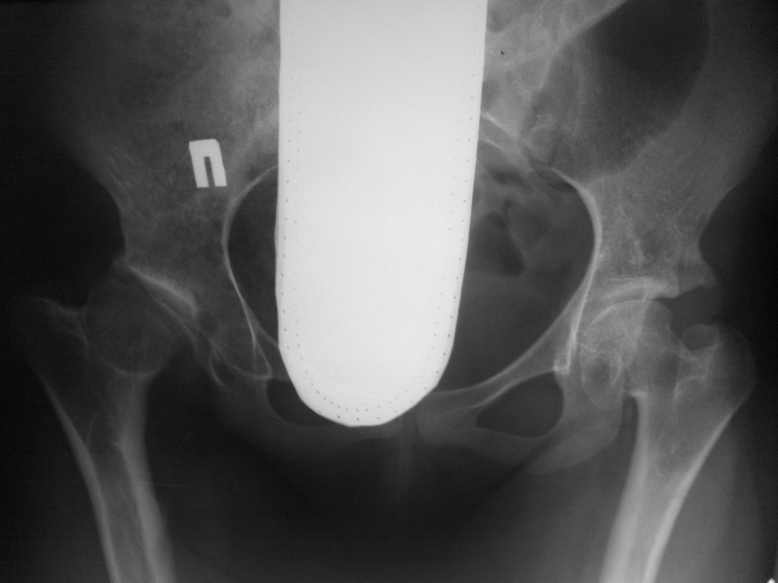

Обратилась девушка 16-ти лет с жалобами на боли в правом тазобедренном суставе

Из анамнеза известно; у пациентки легкая форма ДЦП , в возрасте 5-ти лет ребенок был прооперирован по поводу врожденного вывиха бедер.Клинически ; движения в правом суставе ограничены( сгибание 80,отведение 25, ротация 10-0-5.)Посоветуйте тактику лечения.С уважением Ihor.

Ув.Ihor! 1.Непрямое МРТ контрастирование с гадолиниумом.2Если сохранена "биохимия" суставного хряща впадины то периацетабулярная остеотомия по Ганцу или тройная по Соколовскому с ревизией губы и остеохондропластикой (V образным иссечением остеохондрального перехода шейка-головка". Вторым этапом, или если позволяет кровопотеря одновременно: подвертельная (чтобы не "натягивать" m.iliacus)вальгизирующая остеотомия (цель: длинный диаметр овальной головки "выставить" горизонтально, а не параллельно входу во впадину (принцип Bombelli)). При дооперационной силе абдукторов не ниже 3 баллов можно проводить латерализацию дистального фрагмента (1 см латерализации минус 10% нагрузки на сустав) применяя 130° single angled blade plate